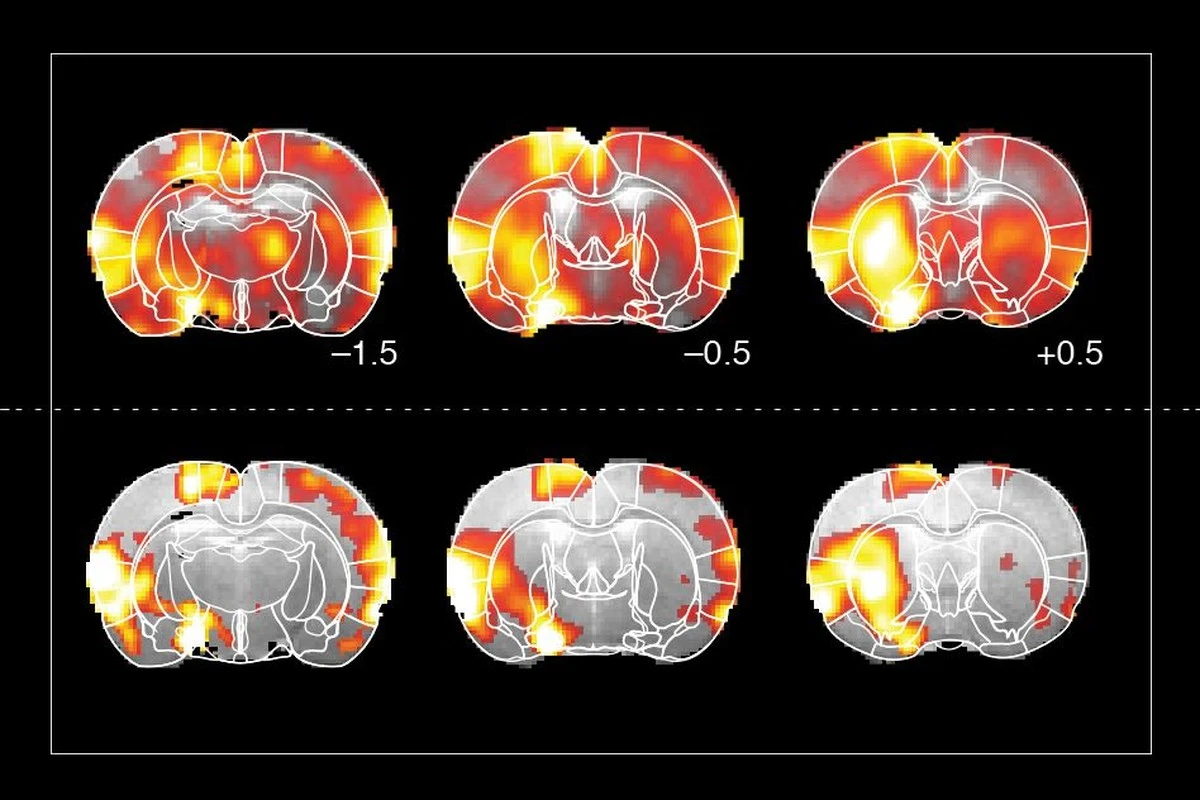

V čem byl tento výzkum jiný? Vědci se zaměřili na specifickou část mozku:

- Sledovali takzvané bazální ganglia, která řídí motoriku.

- Použili technologii DaT SPECT, která se běžně používá jen u seniorů.

- Zkoumali mladé dospělé ve věku 18 až 24 let, tedy desítky let před obvyklým nástupem nemoci.

Anomálie, které nikdo nečekal

Při skenování mozků 12 mladých lidí s autismem vědci narazili na něco překvapivého. U třetiny z nich vykazovaly transportéry dopaminu nenormální chování. To znamená, že proces „recyklace“ dopaminu u nich nefungoval standardně. Zajímavé je, že tito lidé přitom neměli žádné problémy s IQ nebo motorikou, které by je odlišovaly od ostatních.